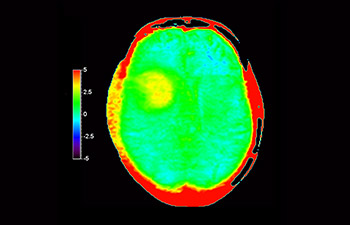

Cerebro con glioblastoma

con 3D APT